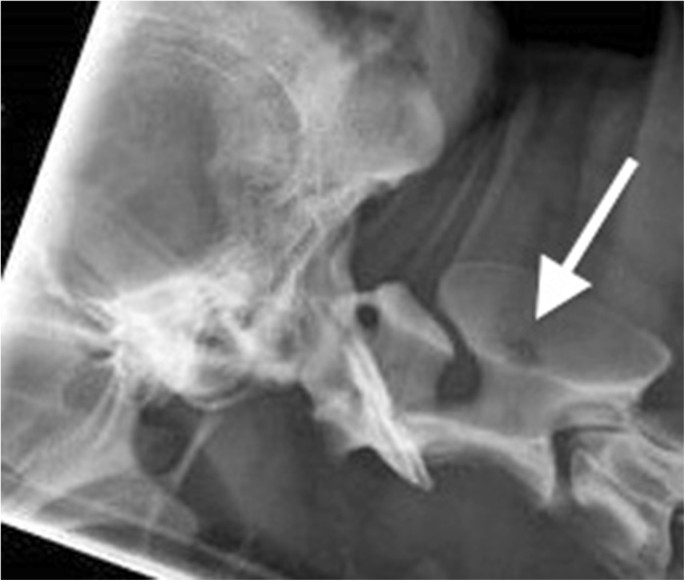

Radiographs of the right hock and thoracic spine showed focal areas of osteolysis and new bone formation within the dorsal arch of the axis, and in the distal 1 cm of the tibial diaphysis, distal fibula and the plantarodistal aspects of the body of the calcaneus (Figures 1 and 2). These findings were suggestive of a neoplastic or infectious process.

Mediolateral and dorsoplantar radiographs of the right tarsocrural joint. There are focal areas of osteolysis in the distal 1cm of the tibial diaphysis, distal fibula (short arrows) and the plantarodistal aspects of the body of the calcaneus. (long arrows). Proliferative active periosteal bone formation is present along the lateral aspect of the calcaneus and distomedial tibial diaphysis and cranio distal tibial diaphysis. A large soft tissue swelling encircles the joint.